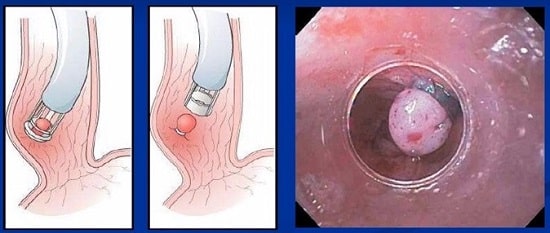

خونریزی واریس مری یک مورد اورژانسی است که نیاز به درمان فوری دارد. بیمار در بیمارستان مقدار زیادی مایعات و خون دریافت میکند تا جایگزین خون از دست رفته شود. دو درمان مختلف غیرجراحی جهت توقف خونریزی واریس وجود دارد: لیگاسیون واریس که از طریق آندوسکوپ و شنت پورتوسیمتیک داخلی کبدی داخل جفتی (TIPS) توسط متخصص رادیولوژیست با تصویربرداری اشعه ایکس انجام میشود.

لیگاسیون واریس

خونریزی واریس مری یک مشکل مرگآور است و در 50% موارد به مرگ بیمار منجر خواهد شد. افرادی که در دورههایی دچار خونریزی واریس مری میشوند، بیشتر در معرض خطر خونریزی دوباره قرار دارند. در 90% از بیماران، درمان با لگاسیون واریس یک روش مؤثر در کنترل خونریزی در مرتبه اول است. با این حال، حدود نیمی از بیمارانی که با لگاسیون واریس درمان میشوند، یک دوره دیگر خونریزی در طول 1 تا 2 سال را تجربه میکنند. مدیتیشن و تغییرات سبک زندگی میتوانند به کاهش خطر بروز مجدد(بازگشت خونریزی) کمک کنند. پیوند کبد تنها در مراکز انتخابی در سراسر کشور که ضوابط بسیار سختی را در نظر میگیرند، انجام میشود.

باندهای مری چقدر ماندگاری دارد؟

پزشک ممکن است هر از دو تا چهار هفته و سه تا چهار جلسه باندهای مری را تکرار کند. باند واریس نیاز به نظارت دارد، بنابراین لازم است که مراجعه به پزشک را از یک تا چهار مرتبه در هر سال را برنامهریزی کنید.

آیا باند مری دردناک است؟

درد پس از لگاسیون باند مری یکی از عوارض شایع است که معمولاً شدت آن خفیف تا متوسط است اما ممکن است در برخی موارد شدید باشد. معمولاً این درد بطور خودبخود برطرف میشود اما ممکن است نیاز به مداخله درمانی جهت تسکین آن باشد.